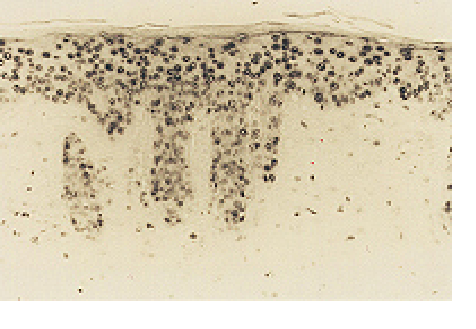

Anti 8-OHdG monoclonal antibody (N45.1) - 20 ug